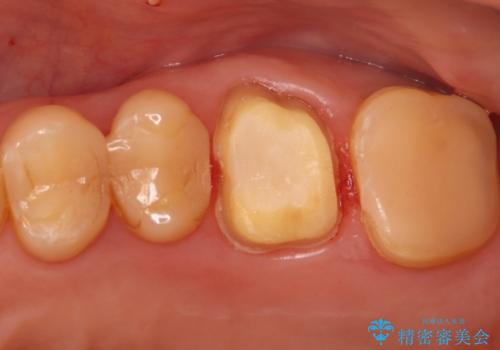

- 右上の歯の痛みを主訴にご来院されました。精密な診査の結果、虫歯が深く進行し、歯の神経(歯髄)にまで炎症が及んでいると診断。このままでは痛みが治まらず、歯を失うリスクもあるため、まず痛みの原因である感染した神経を取り除く根管治療を提案しました。根管治療によって歯の土台を整えた後、歯の破折を防ぎ長期的に機能させるため、**クラウン(被せ物)**を装着して修復する治療計画を立案しました。

治療はまず、感染源を徹底的に除去する根管治療から開始しました。治療の精度を高めるため、ラバーダムや顕微鏡などを使用し、根管内を丁寧に清掃・消毒。これにより、痛みの原因を根本から取り除きました。

根管治療が完了し、歯の内部が清潔で安定した状態になった後、歯を保護し、強い咬合力に耐えられるよう**クラウン(被せ物)**を装着しました。クラウンは、患者様の希望や咬み合わせの状態に応じて、機能性・審美性に優れた素材を選択し、精密に作製しました。